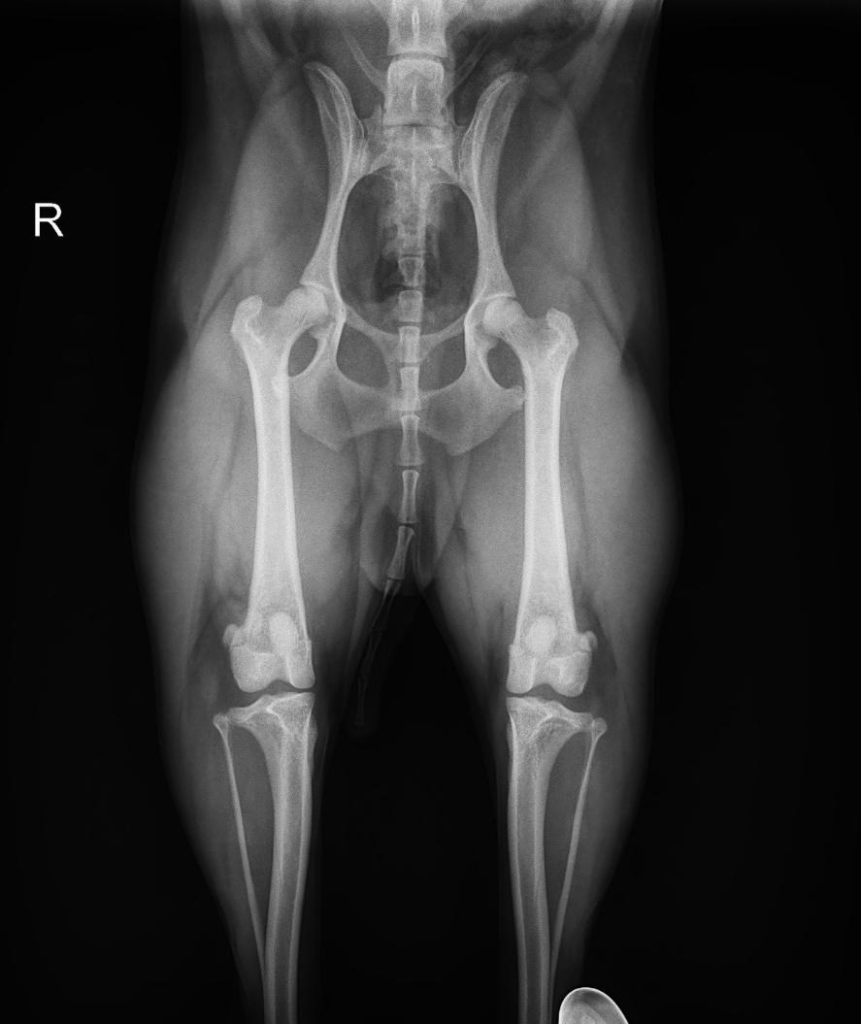

正常な股関節

股関節は、「骨盤側の寛骨臼」と「大腿骨の骨頭」がボールとポケットのようにはまり込んで構成されています。この構造があるからこそ、スムーズな歩行や走行が可能なのです。